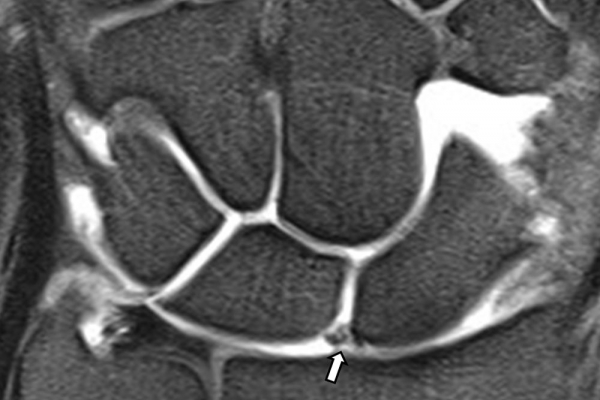

Είναι μια ελάχιστα επεμβατική απεικονιστική μέθοδος που επιτρέπει τη λεπτομερέστερη διερεύνηση του εσωτερικού των αρθρώσεων. Η ασφαλής έγχυση σκιαγραφικού εντός της άρθρωσης υπό ακτινολογική καθοδήγηση και η ακόλουθη απεικόνιση της άρθρωσης με αξονική ή μαγνητική τομογραφία (ή και με συνδυασμό των μεθόδων) αποσαφηνίζει βλάβες του χόνδρου και κακώσεις-ρήξεις συνδέσμων και τενόντων με υψηλή ακρίβεια, συμβάλλοντας σημαντικά στο λεπτομερή χειρουργικό σχεδιασμό.